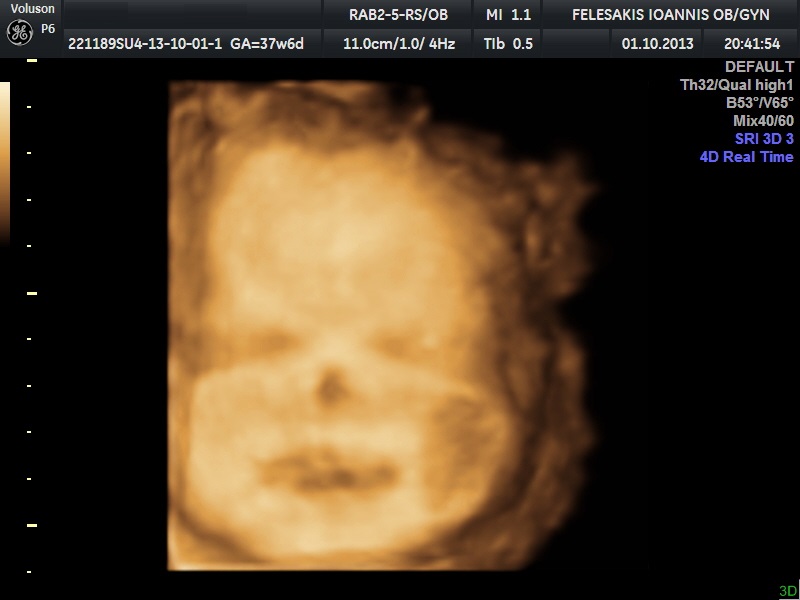

Είναι μία εντυπωσιακή απεικόνιση του εμβρύου μέσα στο "δικό του χώρο". Υπάρχει η δυνατότητα στατικής απεικόνισης όσο και "realtime".Τα αποτελέσματα απεικονίζονται σε ψηφιακή μορφή και αποτελούν επί της ουσίας τη πρώτη οπτική επαφή του ζευγαριού με το έμβρυο.